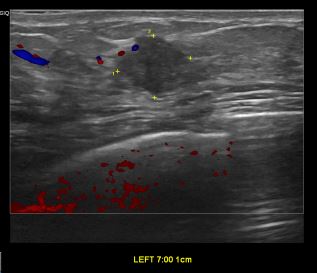

상기환자 좌측에 만져지는 멍울있어 내원하신 30대 여성분으로

좌측유방 혹 총조직검사 시행해 유방암 진단되었습니다.